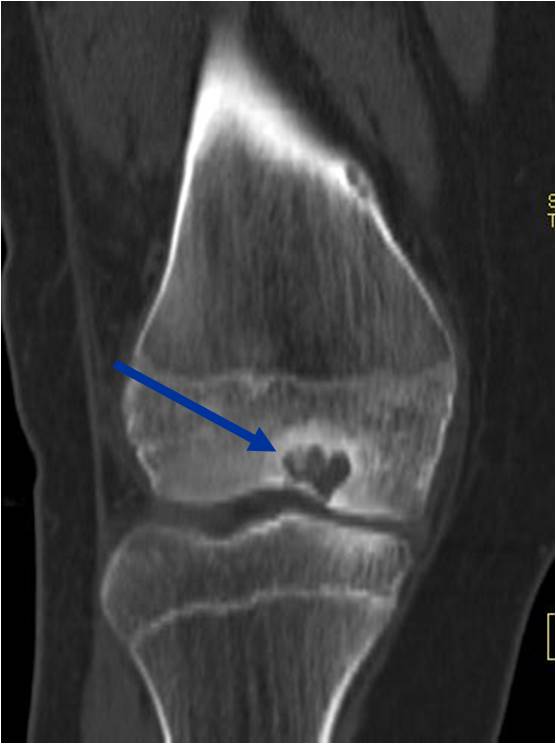

General Information Enchondroma is a benign indolent intramedullary hyaline cartilage neoplasm Accounts for 10% of all benign osseous tumors Limited growth, most lesions are less than 5 cm in maximal dimension Bones grow from a cartilaginous growth plate that...